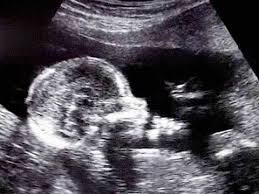

You can see hands, feet, eyes, and ribs. At 17 weeks pregnant, your baby is putting on some fat and gaining muscle. Baby's eyes are opening and she's gaining weight. Total length 17 inches.weight, 3 pounds. This photo shows a baby at 16 weeks of gestation during the second trimester of pregnancy.

Suction aspiration, or vacuum curettage, is the abortion technique used in most first trimester abortions. At this stage, your baby might measure just over five inches long, crown to rump, and weigh about five ounces. The average weight of a baby is about 135 g. When you're 17 weeks pregnant, the fetus is about the size of a pear! What to do in week 17. The baby begins to form a substance called meconium, which is the first bowel movement. Tissues including bones and muscles continue to form. At week 17 the fetus is actively gaining weight and growing.

Pregnancy baby womb baby in womb teratogenicity illustration fetal development week 9 baby unborn pregnant of twins pregnancy week 4 baby in uterus embryo baby womb. I just saw the picture after 3 years and looked up fetal images at 8 weeks and somehow stumbled upon this tragic video. At 15 weeks, roman and other preborn children just need a handful of weeks to grow in their mother's wombs until they reach viability. Suction aspiration, or vacuum curettage, is the abortion technique used in most first trimester abortions. See fetus stock video clips. After meeting while praying on the sidewalk of an abortion facility, edward garcia, a single father of two, and i, a single mother of two, married. And the height is about 12 cm. When life published lennart nilsson's photo essay drama of life before birth in 1965, the issue was so popular that it sold out within days. Miscarried at 13 weeks and 4 days, baby nathan isaiah's short life inside the womb affirms the humanity of the preborn at the earliest stages of life. Baby development at 17 weeks. This photo shows a baby at 16 weeks of gestation during the second trimester of pregnancy. Week 17 of your pregnancy. Our content is doctor approved and evidence based, and our community is moderated, lively, and welcoming.

The baby begins to develop translucent skin. Pregnancy baby womb baby in womb teratogenicity illustration fetal development week 9 baby unborn pregnant of twins pregnancy week 4 baby in uterus embryo baby womb. Mother's powerful photos of baby miscarried at 16 weeks show humanity of preborn children. The size of the fetus at 17 weeks pregnant. Beyond the eighth week of pregnancy, the embryo is called a fetus. Incredible real photos of the human developing in the womb. Length, 10 3/4 inches, crown to rump; This photo shows a baby at 16 weeks of gestation during the second trimester of pregnancy. Suction aspiration, or vacuum curettage, is the abortion technique used in most first trimester abortions. Big bellies at 17 weeks 3 days pregnant. The average weight of a baby is about 135 g. Week 17 of your pregnancy. The mirror reports brooklen nicole spent more than 24 weeks in the womb, but a problem with her placenta.

The baby begins to form a substance called meconium, which is the first bowel movement. Our content is doctor approved and evidence based, and our community is moderated, lively, and welcoming. Where is the baby located at 17 weeks pregnant? When you're 17 weeks pregnant, the fetus is about the size of a pear! And the height is about 12 cm. The mirror reports brooklen nicole spent more than 24 weeks in the womb, but a problem with her placenta. At 8 weeks, the baby looks even more human. Babycenter is committed to providing the most helpful and trustworthy pregnancy and parenting information in the world. This photo shows a baby at 16 weeks of gestation during the second trimester of pregnancy. You'll have your second scan, known as the 'fetal anomaly scan' between 18 and 21 weeks. At 10 weeks, the fetus has a very recognizable. If you had to deliver prematurely now, there is a good chance the baby. Suction aspiration, or vacuum curettage, is the abortion technique used in most first trimester abortions.